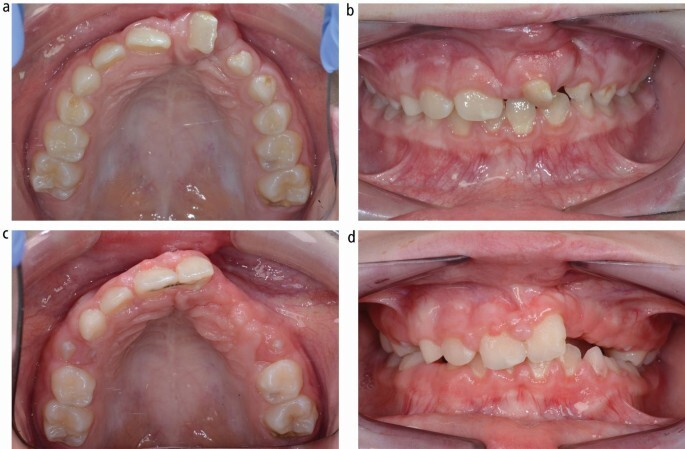

Q

• 10 year old patient

• MIH in upper and lower molars permanent molars

• Anterior tooth wear (NCTSL)

• Upper moderate crowding

• Lower mild crowding